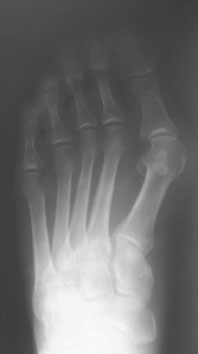

Following heel strike, the subtalar joint pronates, the calcaneus everts and the talus plantarflexes and adducts. Excessive movement in the direction of pronation results in the foot losing its ability to resupinate with ultimate collapse of the medial arch. The purpose of arthroereisis devices is to limit excess subtalar joint motion in the direction of pronation and still allow the joint to supinate. Chambers first described the concept of using an implant to limit subtalar joint motion in 1946. He used a bone graft to elevate the floor of the sinus tarsi in order to prevent subtalar joint eversion.1 Many have followed with various arthroereisis implant devices. Smith popularized the procedure in the podiatric profession in the early 1970s with the development of the STA-Peg.2 This polyethylene implant sat in the floor of the sinus tarsi and allowed the talus to move forward but at an oblique angle to the joint surface. This limited STJ motion by its “axis-altering” properties. Although the implant was originally cemented into the calcaneus to prevent loosening, this technique was discontinued due to potential complications associated with the use of bone cement although no adverse consequences were noted. Subsequently, a number of implants have emerged over the years. The majority of these subtalar implants occupy the soft tissue content of the sinus tarsi in order to limit the anterior movement of the talus on the calcaneus. Green, et. al., offered a comprehensive review of this procedure and other devices earlier this year.3 Maxwell and Brancheau developed the MBA implant nearly 15 years ago as an alternative arthroereisis device for people with flexible flatfoot deformity.4,5 This is a “free floating” device in the sinus tarsi that “blocks” anterior talar movement. The device’s ease of insertion, lack of complications and overall benefit has made this one of the most commonly used implants in foot surgery. Over the years, multiple studies have documented the success of the arthroereisis procedure in children and, more recently, in adults.4-7 Needleman recently published a retrospective study of the MBA implant in the adult flatfoot and reported a 78 percent satisfaction rate.6 The most common complication in this study was sinus tarsi pain, which occurred in 13 of 28 feet (46 percent). This complication required implant removal in 11 patients but none of these implants were removed earlier than eight months postoperatively. Interestingly, radiographic parameters after implant removal remained unchanged with no loss of correction. Perhaps the most commonly reported complication of arthroereisis procedures is sinus tarsi pain, which occurs in 5 to 10 percent of patients.8 This often resolves with rest, casting, orthotics, cortisone injection or a combination thereof. The prevailing thinking is this pain is both a reactive synovitis and bone contusion from the significant compressive forces generated by and upon the implant. Poor implant sizing, implantation and loosening may play a role as well. These findings appear to be much more common in the adult than in the juvenile patient. Recently, Kinetikos Medical has released the resorbable bioBlock® arthroereisis implant. This is a near duplicate of the MBA implant in terms of shape, design and the method of implantation. It is made of poly-L-lactic acid (PLLA) and is therefore radiolucent. Once one has inserted the implant, the clinician can obtain an X-ray with the driver in place in order to assess the final position of the implant. Its resorption characteristics are still unknown. According to the company, an 8 mm implant placed in a saline bath to simulate the body’s environment demonstrated no loss of mechanical strength at eight months. However, much is known about PLLA and other bioresorbable materials.

Various authors have reported a wide range of applications for bioabsorbable implants in the literature, including the use of these modalities in osteotomies, fractures and arthrodeses. However, the surgeon must remember that in comparison to traditional metal implants, bioabsorbables possess inferior mechanical properties.18 Therefore, surgeons should reserve the use of these implants for instances when minimal load and stress will be applied, when healing will occur before the implant loses significant strength, and when surgeons would remove the implant under normal circumstances.9 Medial malleolar fractures and syndesmotic injuries are currently the most accepted applications for absorbable fixation. Bucholz, et. al., randomized 155 patients with displaced medial malleolar fractures.19 They managed one group with 4.0 mm stainless steel fixation while managing the other group with 4.0 mm PLA screw fixation. There was no significant difference between the groups in terms of fracture healing, postoperative complications or functional results. In addition, at an average follow-up of 37 months, no inflammatory reactions occurred in the PLA group. Hovis, et. al., followed 23 patients with PLLA screw fixation of syndesmotic injuries for an average of 34 months.18 All patients returned to pre-injury levels of activity within the time of follow-up. There were no reactions to the absorbable material and no secondary procedures were required. The authors conclude that PLLA screws are ideal for fixation of these injuries because compression is not required in syndesmotic repairs. Thordarson, et. al., compared bioabsorbable fixation to stainless steel screw fixation of syndesmotic injuries in pronation-external rotation ankle fractures.20 In a randomized study, the authors utilized fixation with a 4.5 mm PLA screw for 17 patients and employed a 4.5 mm stainless steel screw for 15 patients. After 11 months, all fractures healed uneventfully. In addition, there were no wound complications, no radiographic osteolytic changes and no inflammatory reactions in the PLA group. The Lisfranc injury represents another clinical scenario in which approximation has more vital importance than compression. These injuries also typically require hardware removal after standard open reduction internal fixation (ORIF) with metal implants. Accordingly, Lisfranc injuries seem extremely conducive to bioabsorbable fixation. Thordarson and Hurvitz used PLA screws in 14 patients with Lisfranc fractures/dislocations.21 There was no loss of reduction after an average 20-month follow-up. There were also no reports of soft tissue or bone reaction to the implants. Within a 10-year period, Rokkanen, et. al., performed a total of 2,500 orthopedic procedures using bioabsorbable materials.22 They reported fixation failure in 3.7 percent of the patients with PGA implant cases and encountered non-infectious inflammatory reactions in 2.3 percent of patients with PGA implants. The reaction appeared postoperatively at two to three months. However, no reactions occurred with the use of PLA implants. Bioabsorbable implant use in pediatric patients is still under debate. Researchers published an experimental study on the effect of PDS implants placed across the growth plate of rabbits in 1989.23 A transphyseal 2.0 mm PDS implant showed no permanent growth disturbance and no histomorphometric change in comparison to a control. Böstman, et. al., published a study of PGA pins in treating 71 fractures in skeletally immature patients. According to the study, 87 percent of patients experienced anatomic healing until union.17 Still, the authors recommended long-term clinical studies before widespread use becomes commonplace for pediatric patients. However, keep in mind that these studies dealt with implanting devices into bone as opposed to soft tissues. There are two publications on results with resorbable sinus tarsi implants. Giannini initially reported on a four-year follow-up of an absorbable sinus tarsi implant.24 The study evaluated the Stryker Howmedica PLLA bioabsorbable subtalar implant, which is not available in the United States. The authors treated 21 children with flexible flatfoot. The children ranged from 8 to 15 years of age. The researchers performed Achilles tendon lengthening in six feet and performed a modified Kidner in 12 feet. In a four-year follow-up study, the authors reported that only 5 percent of the patients had pain as opposed to 81 percent of patients who had preoperative pain.24 Whether this pain was related to the implant is not clear. No implants had to be removed. The authors of the study obtained sequential MRIs from three months to five years postoperatively. There was no sinus formation or osseous changes. Changes in implant resorption began to show at six months and fragmentation was noted at one year. However, the overall structure appeared to remain intact. A loss of structural integrity with fragmentation occurred by 18 months. The authors of the study saw complete resorption at four years postoperatively.24 The only reported complication was impingement of implant fragments against the shoe in two patients at one and two years postoperatively. Both resolved with the complete resporption of the material. Keep in mind that the design of the Stryker Howmedica PLLA bioabsorbable subtalar implant is considerably different than the bioBlock implant, which is available in the U.S. Most recently, Giannini, et. al., published a study involving 12 patients (14 feet). For these patients, they resected a tarsal coalition in the middle facet of the subtalar joint and subsequently implanted the Stryker absorbable sinus tarsi implant to correct the symptomatic flatfoot.25 All patients presented with hindfoot pain preoperatively and only 5 percent had this pain postoperatively. The results showed eight excellent, three good and three fair results subjectively with AOFAS scores improving in all 14 feet based on pain reduction, hindfoot alignment and ROM.25 There was no discussion of the implant other than its value in correcting a pronated foot.

To answer the question of whether bioresorbable implants work, the answer appears to be yes. Although there are only two published studies on bioresorbable implants in juveniles, both of which are favorable, the design characteristics of the bioBlock implant are nearly identical to those of the well documented MBA implant. Accordingly, one would expect similar results. As to the question of whether the bioBlock implant is better, the answer is unclear at this time. The company states that one potential advantage is for parents who do not want a permanent metallic implant in their child’s foot. Although this is true, this concern is only raised in a small number of patients. As noted earlier, subtalar joint pain is the most common complication of arthroereisis devices. If we assume the implant was the correct size and was properly inserted, will resorbable implants lower this complication rate? Sinus tarsi pain is, in part, a reactive inflammatory response secondary to the compressive forces between the talus, calcaneus and the interposed implant device. As the implant begins to resorb and lose its structural integrity, these forces should diminish with subsequent reduction of clinical symptoms. Needleman noted that, in most patients, the sinus tarsi pain began shortly after weightbearing and ultimately required removal in 9 of 12 feet between seven and 12 months postoperatively.6 Therefore, if the implant does not lose its structural integrity until 18 months postoperatively in children as reported by Giannini, the implant will probably not resorb quickly enough to prevent its removal secondary to sinus tarsi pain.24 Resorption times for bioabsorbable subtalar joint implants are unknown in adults but probably exceed that of children due to decreased vascularity. Kinetikos Medical recommends maximum patient body weights for each diameter implant. For an 8 mm implant, the maximum body weight would be 150 lbs. For a 9 mm implant, it would be 180 lbs. For a 10 mm implant, it would be 220 lbs. For an 11 mm implant, it would be 250 lbs. For a 12 mm implant, it would be 250 lbs. Exceeding these limits may cause the implant to deform. It is unlikely this alteration of shape will result in loss of correction but it may reduce compressive forces within the sinus tarsi. Additionally, the implant, due to its viscoelastic properties, does have the capacity to deform under pressure. These factors may lessen the incidence of sinus tarsi pain. Loosening is rarely a problem with most sinus tarsi implants that are properly inserted. Soft tissue ingrowth helps to stabilize these implants, which are not inserted into bone. Scar tissue encompasses the implant and occupies the spaces between the threads and central cannula. With resorbable implants, as the structure loses its integrity, this stability will be lost and implant loosening may occur. If removal of the implant or its fragments is required, this could prove difficult as the material is radiolucent. Although the incidence of adverse reactions to PLLA is less than 1 percent, foreign body reactions are still possible, especially when the implant fragments and shards are dispersed into the soft tissues. The final and perhaps most important question to consider is the long-term efficacy of resorbable sinus tarsi implants for the correction of flatfoot deformity. Needleman demonstrated no significant change in radiographic parameters after implant removal at an average follow-up time of nearly four years.6 All patients had either a heel cord lengthening and most had adjunctive forefoot procedures so it is difficult to isolate the effect of implant removal. However, these findings are consistent with other reports in the literature (among both adults and children) of persistent correction despite implant removal or resorption. An “arthrofibrosis” of the subtalar joint appears to develop and this may ultimately limit motion in the implant’s absence.